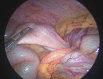

Case presentation: We present the case of a 32-year-old woman with abdominal pain in the right upper quadrant, whose computed tomography revealed an ileocolic intussusception and a low-density tubular image in the distal loop. She underwent diagnostic laparoscopy and laparoscopic right colectomy. Biopsy results confirmed a LAMN with acute appendicitis and intussusception.

Clinical discussion: Appendiceal intussusception (AI) is associated with the alteration of peristalsis, in addition to multiple inflammatory conditions and diseases such as parasites, foreign bodies, Crohn's disease, and lymphoid hyperplasia. The pathophysiology of AI is not fully established, but the main appendicular alteration that has been associated with it is the presence of a tumor. AI lead points are typically pathological in 90 % of cases, 65 % of which are neoplastic in nature. Right hemicolectomy should be performed for tumors involving the periappendicular area or in those larger than 2 cm in size. Follow-up and surveillance colonoscopy is suggested.